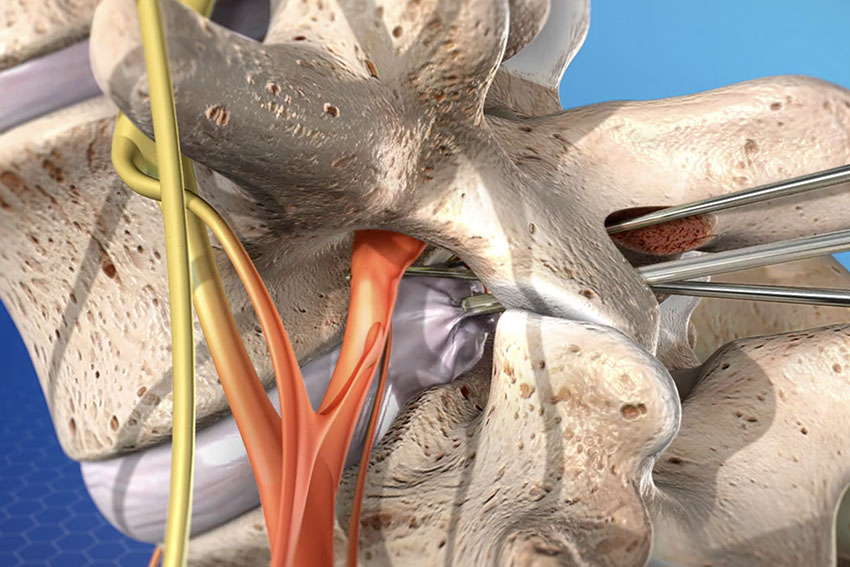

Spinal Fusion

Advanced treatment restoring spine stability, relieving pain, and improving mobility.

Laminectomy

Spine decompression surgery relieving nerve pressure, restoring movement & comfort.